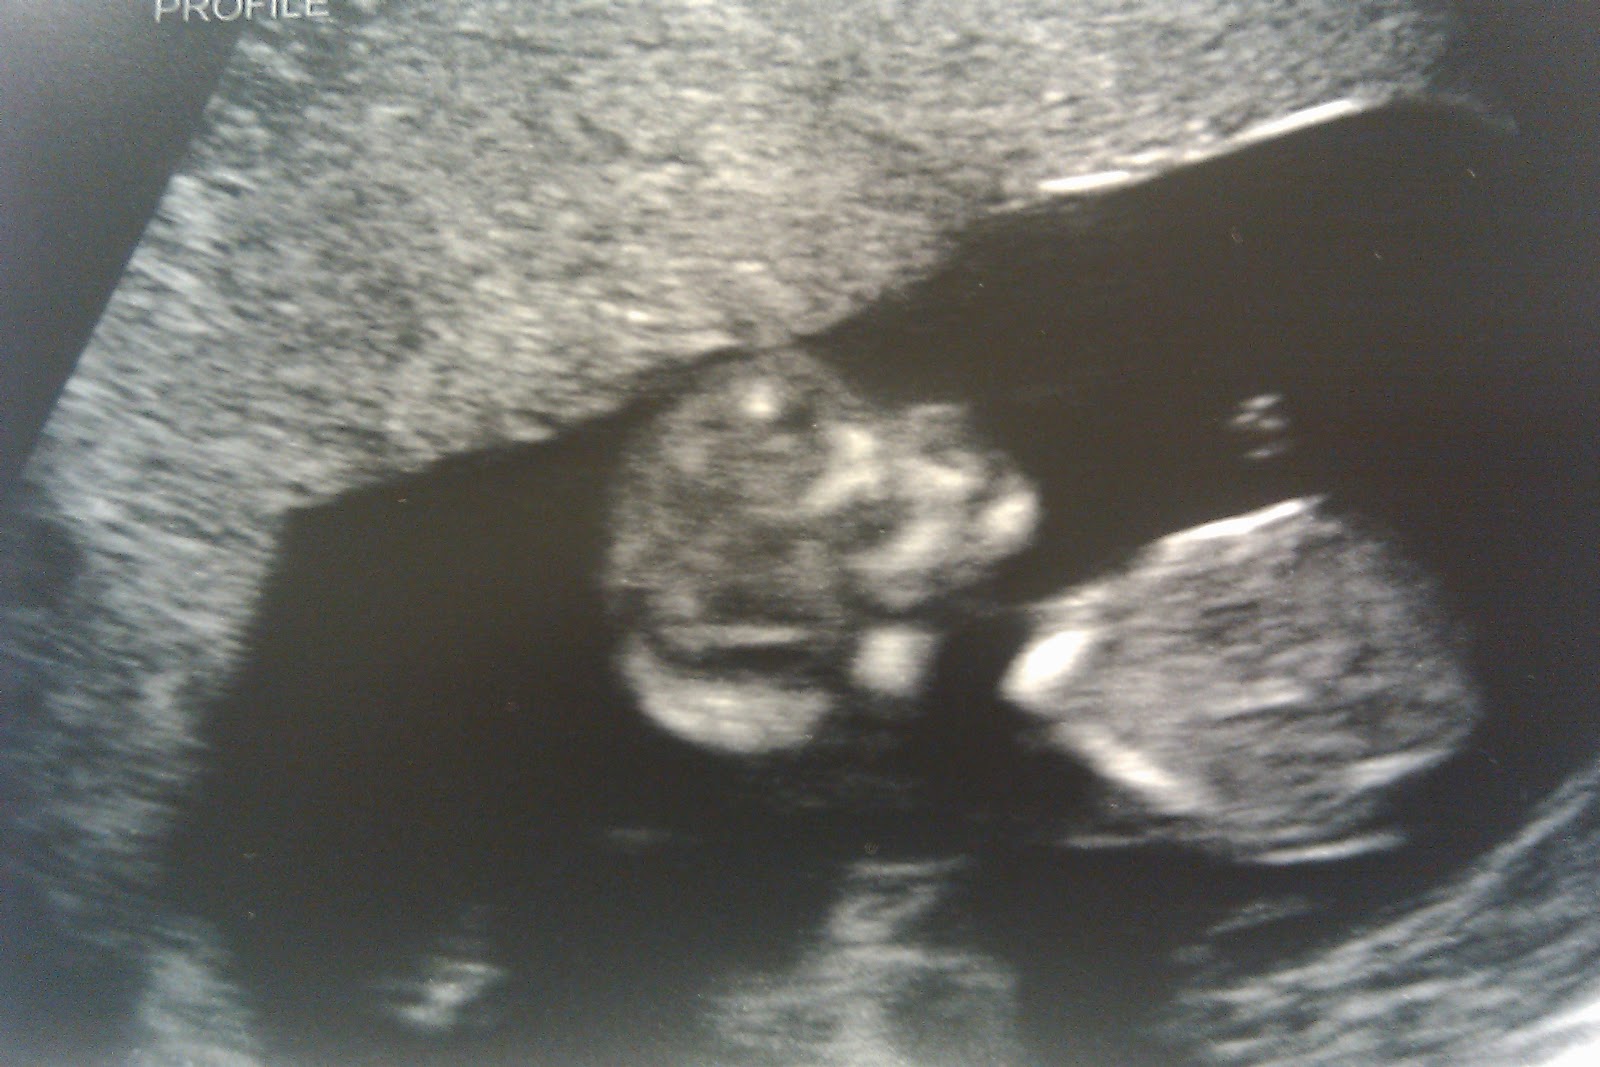

We have to start a little before the day you were born. At the beginning of my pregnancy, before I even knew you were twins, we knew my due date was May 21, 2012. Then when we found out you were twins, the doctor said you would probably be about 3 weeks early, so we went with May 1 as the due date. After a month or two of that, all of the sudden, he said you would probably be about 4 weeks early. We were surprised, but started thinking and telling people your due date would be April 21. I mean, wouldn't you think looking at these that you were squished enough to warrant early release? Kate is on the right and that is Pippa on the left with her own leg folded in front of her. There is some debate if that is actually your leg or your sister's, but that is what the ultrasound tech told us.